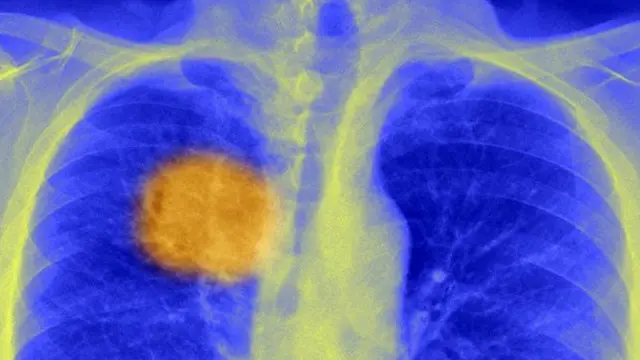

سائنس دانوں کا خیال ہے کہ انھوں نے ایک ایسا طریقہ دریافت کر لیا ہے جس کے تحت جسم کے اپنے دفاعی نظام کو سرطان کے خلیے ختم کرنے کے لیے ’مائل‘ کیا جا سکتا ہے۔

جریدے ’سائنس‘ میں شائع ہونے والی اس رپورٹ کے مطابق محققین نے سرطان کی رسولی میں کچھ ایسے ’کمزور مقامات‘ ڈھونڈ نکالنے کا طریقہ دریافت کر لیا ہے جنھیں انسان کا مدافعتی نظام نشانہ بنا کر مرض کو بڑھنے سے رو کتا ہے۔

مسئلہ یہ ہے کہ سرطان کی رسولی کے خلیے یکساں نہیں ہوتے اور رسولی جینیاتی طور پر تبدیل شدہ خلیوں کا بےہنگم مجموعہ ہوتی ہیں، اور رسولی کے مختلف حصوں کے خلیے ایک دوسرے سے مختلف ہوتے ہیں۔

سرطانی خلیے میں پیدا ہونے والی جینیاتی تبدیلیاں ایک تنے کی مانند ہوتی ہیں جو نیچے سے ایک جیسی ہوتی ہیں لیکن اوپر شاخ در شاخ پھیلتی چلی جاتی ہیں۔

اس تحقیق کے ذریعے ان خلیوں میں پیدا ہونے والی ان بنیادی جینیاتی تبدیلیوں کی ’جڑ‘ دریافت کرنے کا طریقہ تلاش کیا گیا ہے جن کے تحت خلیوں کے اینٹی جینز (antigens) میں بھی تبدیلی آ جاتی ہے۔ اینٹی جینز وہ پروٹینز ہیں جو سرطان کے خلیوں کے باہر چپکی ہوئی ہوتی ہیں۔

یو سی ایل کینسر انسٹیٹیوٹ کے پروفیسر چارلس سوانٹون کہتے ہیں کہ ’یہ بہت خوش آئند بات ہے کیونکہ اب ہم سرطان کے ہر خلیے میں موجود اینٹی جینز کو نشانہ بنا سکتے ہیں اور یہی اینٹی جین وہ کمزور مقام یا ’دکھتی رگ‘ ہیں جسے شناخت کر کے پیچیدہ ترین سرطانوں کا علاج بھی ممکن بنایا جا سکتا ہے۔‘